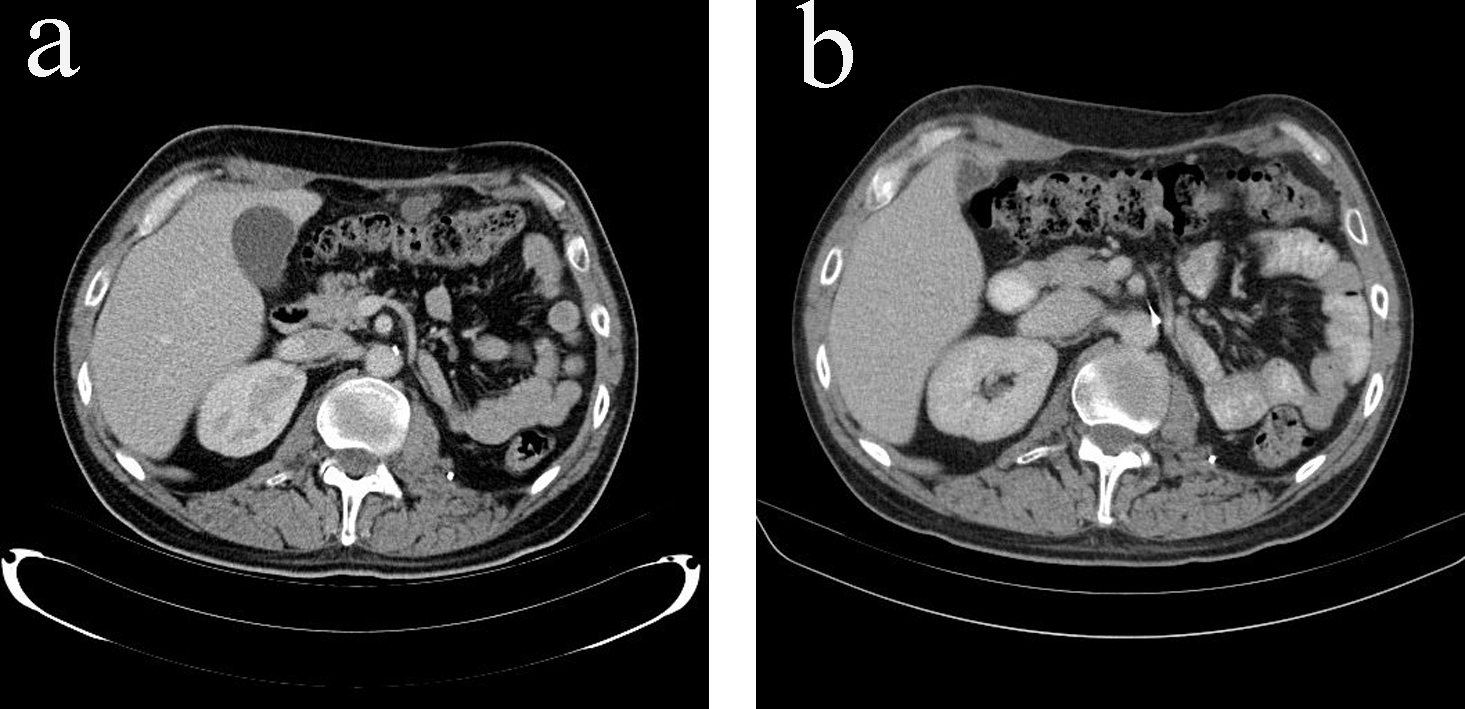

Adjuvant mitotane monotherapy (3 - 6 g/day) together with cortisol replacement was initiated after the surgery. The patient enjoyed disease-free period of 7 months until he developed metastatic disease in bones, lungs and peritoneum (Fig. 4a, 5a). At time of presentation of relapse he was complaining of thoracic back pain which precipitated MRI spine which showed T12 cord compression requiring palliative radiotherapy (30 Gy in 10 fractions). Six cycles of etoposide, doxorubicin and cisplatin (EDP) were added to mitotane over a period of 7 months, resulting in excellent partial response to treatment, i.e. complete response of all peritoneal nodules, near complete response of the multiple pulmonary nodules except one sub-centimeter nodule in each lung and stable bony metastases (Fig. 4b, 5b). The patient is now on mitotane monotherapy only (3 - 6 g/day) with stable disease. Therapeutic enoxaparin was ceased after 27 months of treatment for pulmonary embolism with no further thromboembolic complications.

![]() Click for large image | Figure 5. (a) Peritoneal metastases in CT scan (transverse view) before additional chemotherapy with EDP. (b) Resolution of peritoneal metastases in CT scan (transverse view) after additional chemotherapy with EDP. |